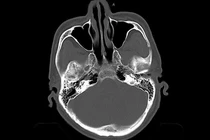

Ở người cao tuổi, một cú ngã tưởng chừng nhẹ cũng có thể gây tụ máu não tiến triển nhanh, các triệu chứng không rầm rộ, nhưng xấu đi rất nhanh.